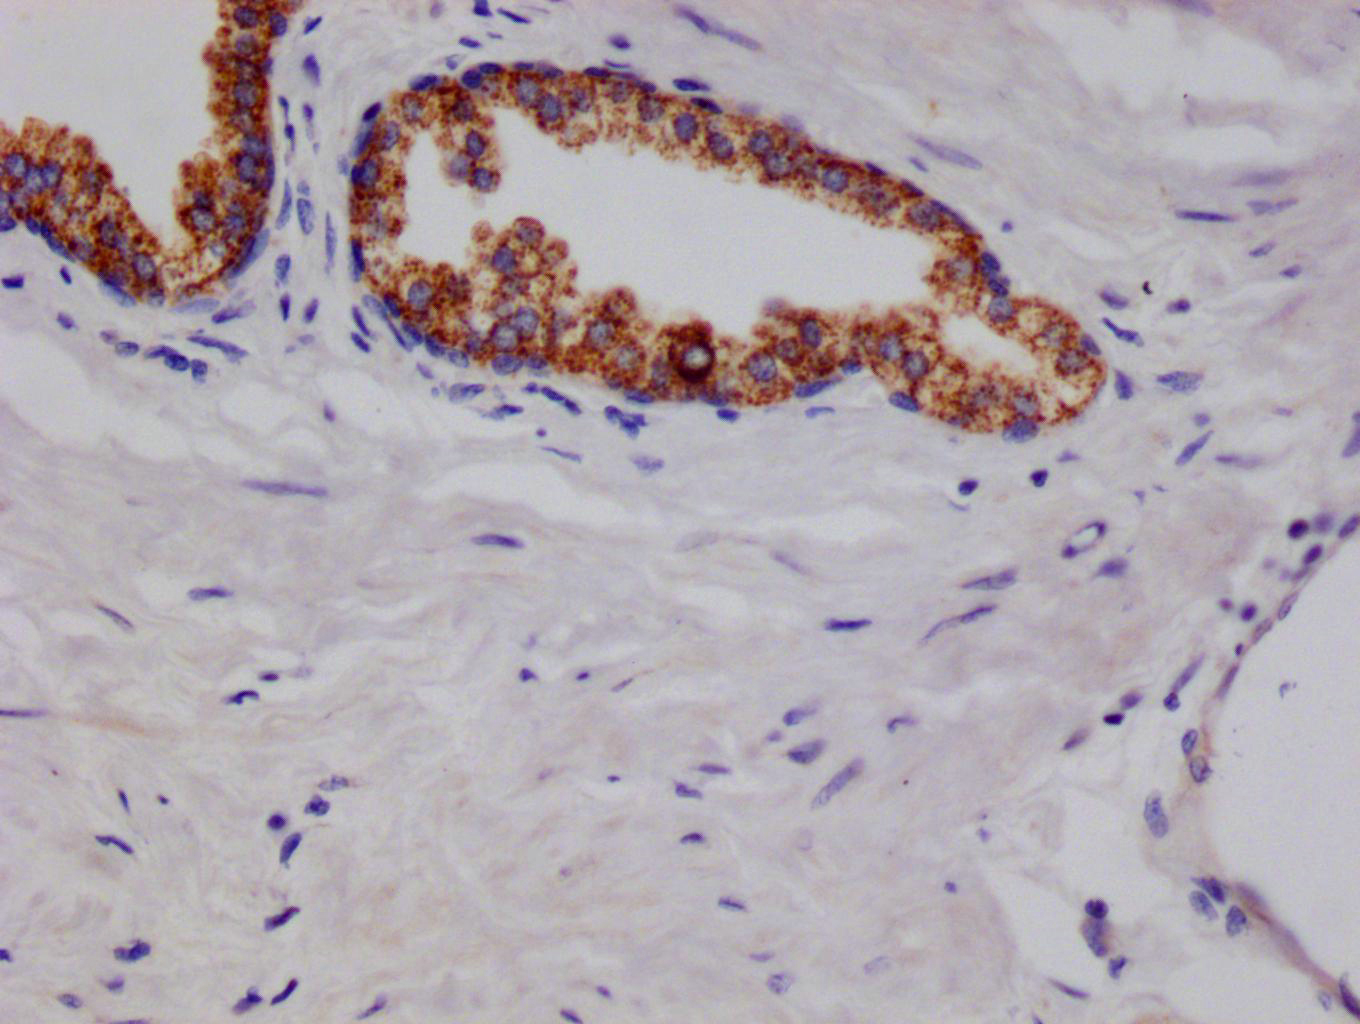

ApplicationELISA, IHC, IF, FC; Recommended dilution: IHC:1:50-1:200, IF:1:50-1:200, FC:1:50-1:200